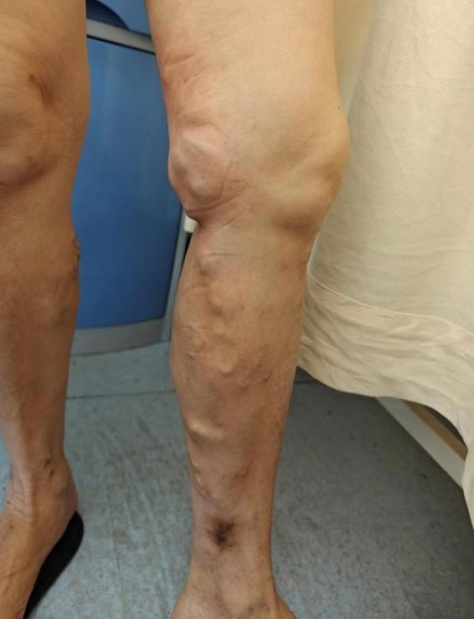

想象一下,我們的血管就像一條條河流,負(fù)責(zé)把血液從腳送回心臟。但有時(shí)候,這些“河流”會(huì)變得蜿蜒曲折,甚至在某些地方變得膨脹,導(dǎo)致血液在腿部滯留。這就像是排水管被堵住了,水流積起來(lái)排不出去,我們腿部那些外觀類(lèi)似于蚯蚓的血管,就是靜脈曲張。

曲張的血管:腿部的血管顏色看起來(lái)很顯眼,彎彎曲曲,就像“蚯蚓”一樣。